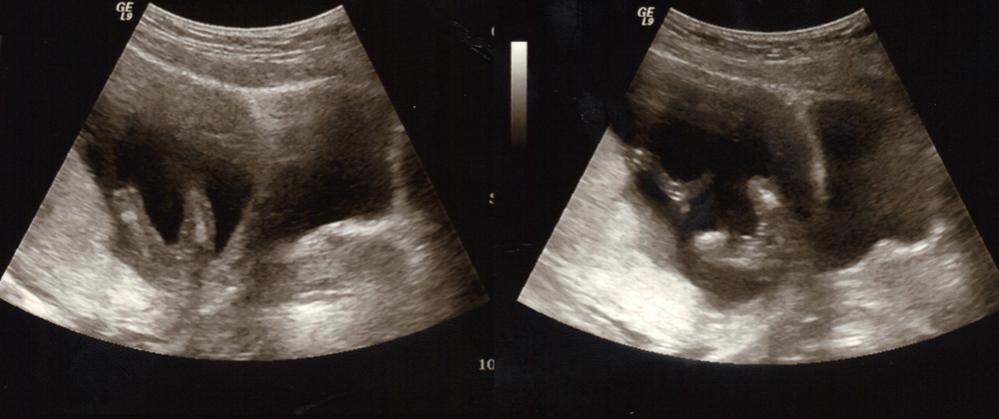

Please take a look at my ultrasound pic I got today. Does this look boy or girl to you? Any guesses would be greatly appreciated!! :)

Thank you guys so much for your guesses!! This is my first baby, and I am so hoping for a girl :) I will confirm Jan 3rd and post in here. :) If it does end up growing a little something extra, I will still love it just as much! But she looked at all angles, and didn't see anything.